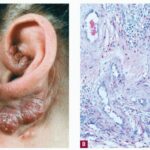

Angiolymphoid hyperplasia with eosinophilia (ALHE) shows characteristic histologic features, including a proliferation of small blood vessels, many of which are lined by enlarged endothelial cells with uniform ovoid nuclei and intracytoplasmic vacuoles. These distinctive endothelial cells have been described as having a cobblestone appearance. In addition, a perivascular and interstitial infiltrate composed primarily of lymphocytes and eosinophils (see the image below) is present. Eosinophils typically comprise 5-15% of the infiltrate. Rarely, they can account for as much as 50% of the infiltrate. Occasionally, the infiltrate is devoid of eosinophils. Lymphoid aggregates with or without follicle formation are typical.